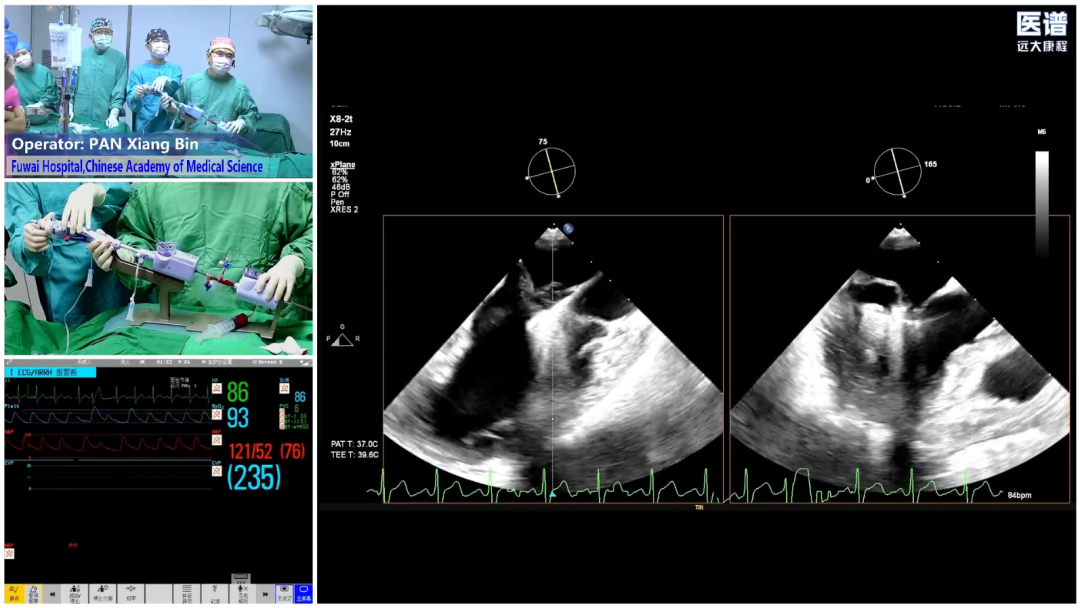

1月22日至24日,亚洲心脏介入领域年度顶级盛会——Singapore LIVE 2026(SingLIVE 2026)在新加坡隆重召开。会议期间,中国医学科学院阜外医院潘湘斌教授团队受邀向大会进行纯超声引导经导管二尖瓣缘对缘修复术(TEER)手术转播,凭借其创新性与高难度引发国际同行的广泛关注,成为本次会议的焦点。

与传统TEER手术依赖射线引导不同,潘湘斌教授团队通过应用中国原创的无辐射介入技术,以超声引导作为底层方法学,成功完成一例纯超声引导下的重度二尖瓣反流、二尖瓣后叶脱垂伴腱索断裂MitraClip-TEER手术,即刻实现反流显著减少,得到了全球顶尖专家的高度认可。这一手术的成功,不仅展现了中国原创技术在国际舞台上的强大实力,更为破解二尖瓣反流治疗难题贡献了真正意义上的一站式、无辐射、精准高效的“中国方案”。

手术过程

患者麻醉后取平卧位,经食管超声(TEE)探头置入到位。股静脉穿刺点消毒铺巾后进行穿刺,并置入鞘管建立工作路径。置入超声引导专用导丝(Panna Wire)和房间隔穿刺针。Panna Wire梭形头端在超声下具有优异的可视性与指向性,将其置入穿刺针内,可实时指导穿刺针的位置。在TEE实时引导下,完成房间隔穿刺。因左心房容积偏小,操作空间受限,故穿刺点选择略靠后,但操作过程顺利,未损伤左心房后壁。

随后将可操控导引导管(SGC)及二尖瓣夹输送系统(CDS)送入左心房。仔细调整XTW二尖瓣夹的轨迹和方向后,进行首次夹合,超声提示仍存在少量二尖瓣反流,考虑为后侧瓣叶捕获不足所致,且侧边瓣叶仍存在明显脱垂。遂打开夹臂,在左心房内调整夹子位置,向后侧、外侧移动,以捕获更多后侧瓣叶,再次夹合,成功解决反流与脱垂问题,测得术后平均压差为4mmHg,手术圆满成功。